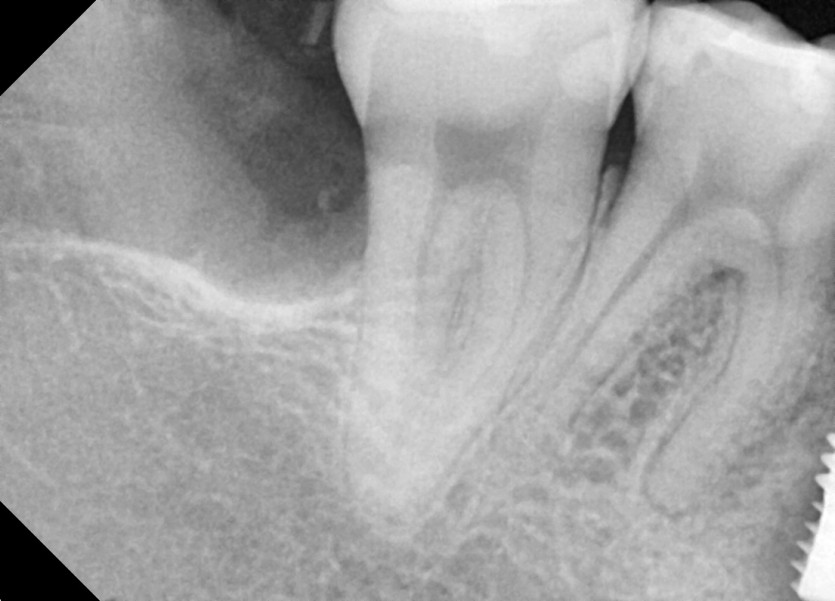

#48 사랑니 발치

구강 외과 전문의가 당일 발치했습니다.